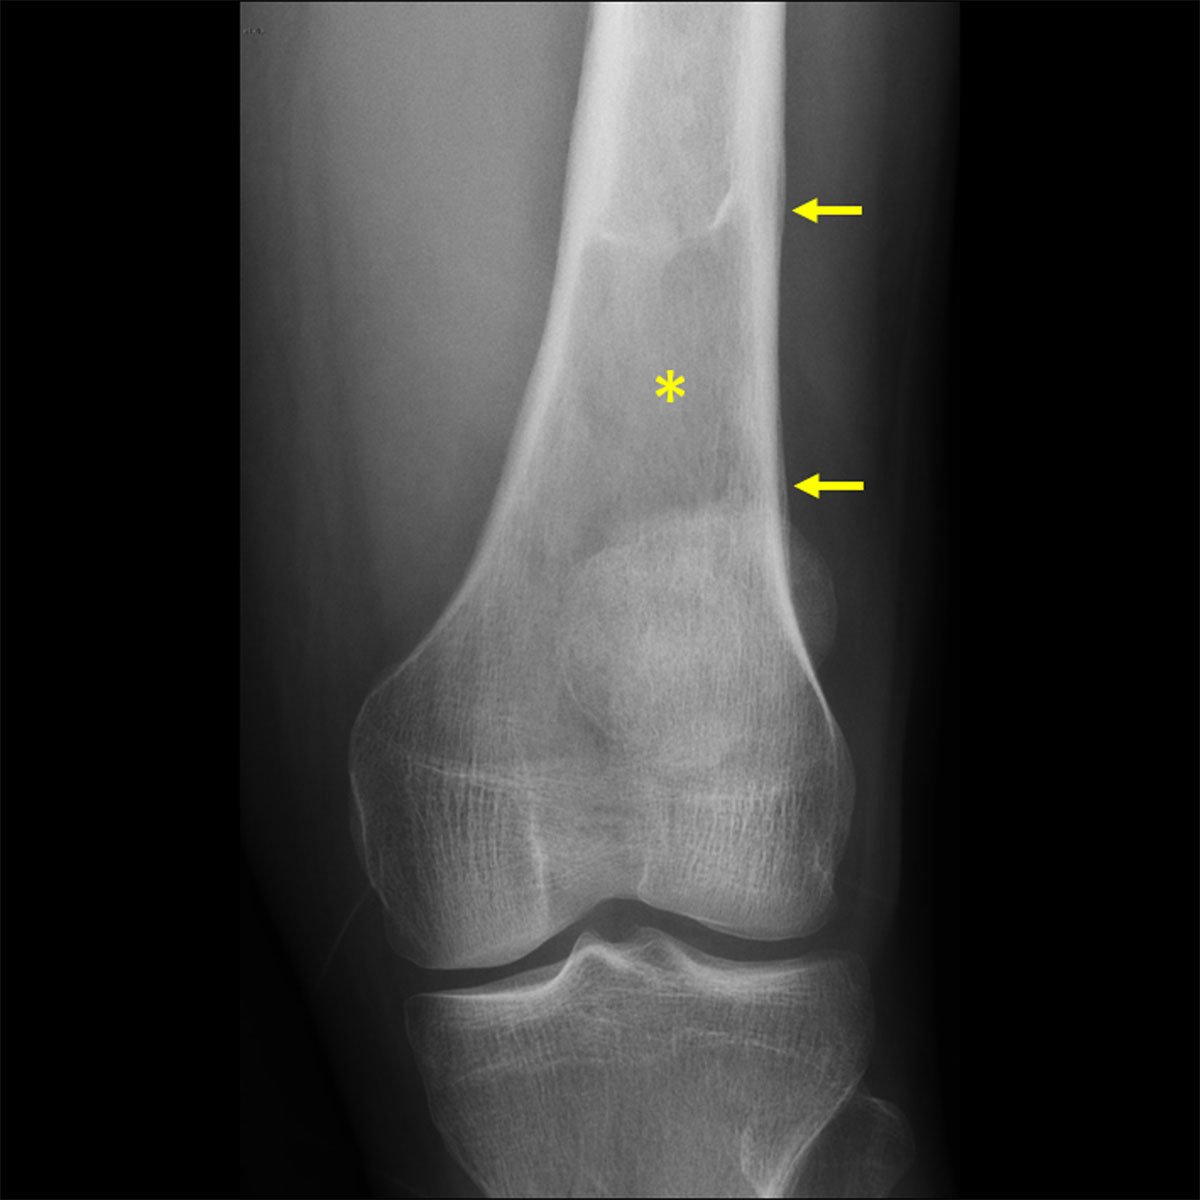

Figure 1

Knee radiograph showing a lytic lesion in the femur with lamellated periosteal reaction.